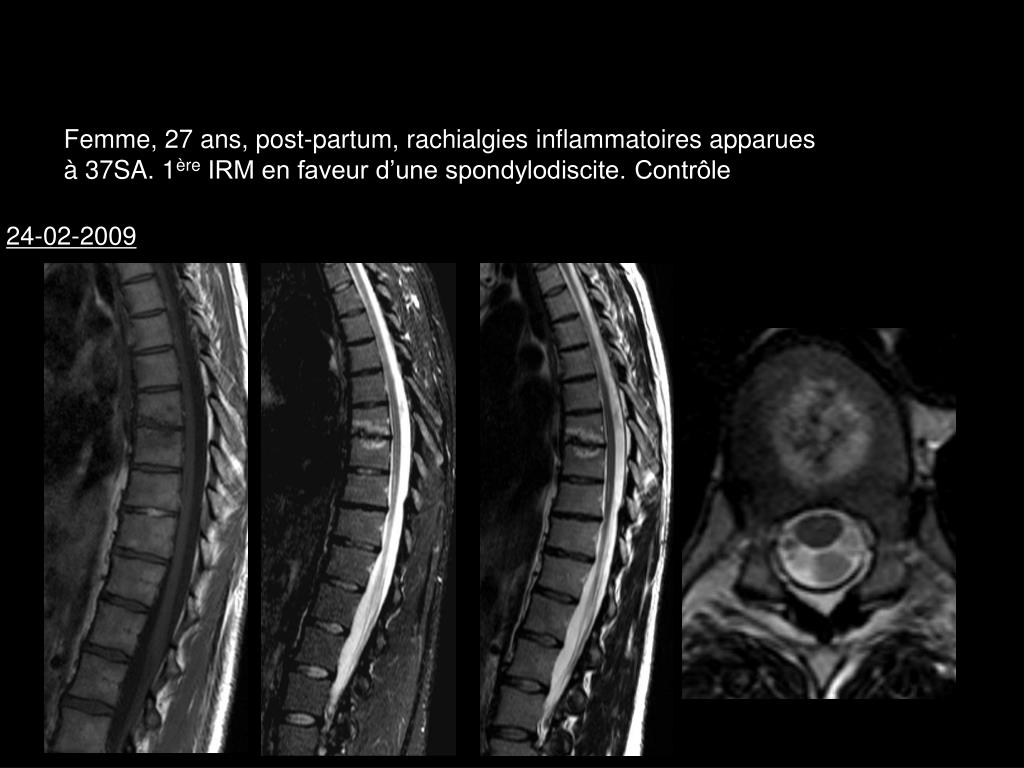

11. Femme, 27 ans, post-partum, rachialgies inflammatoires apparues à 37SA. 1ère IRM en faveur d’une spondylodiscite. Contrôle 24-02-2009